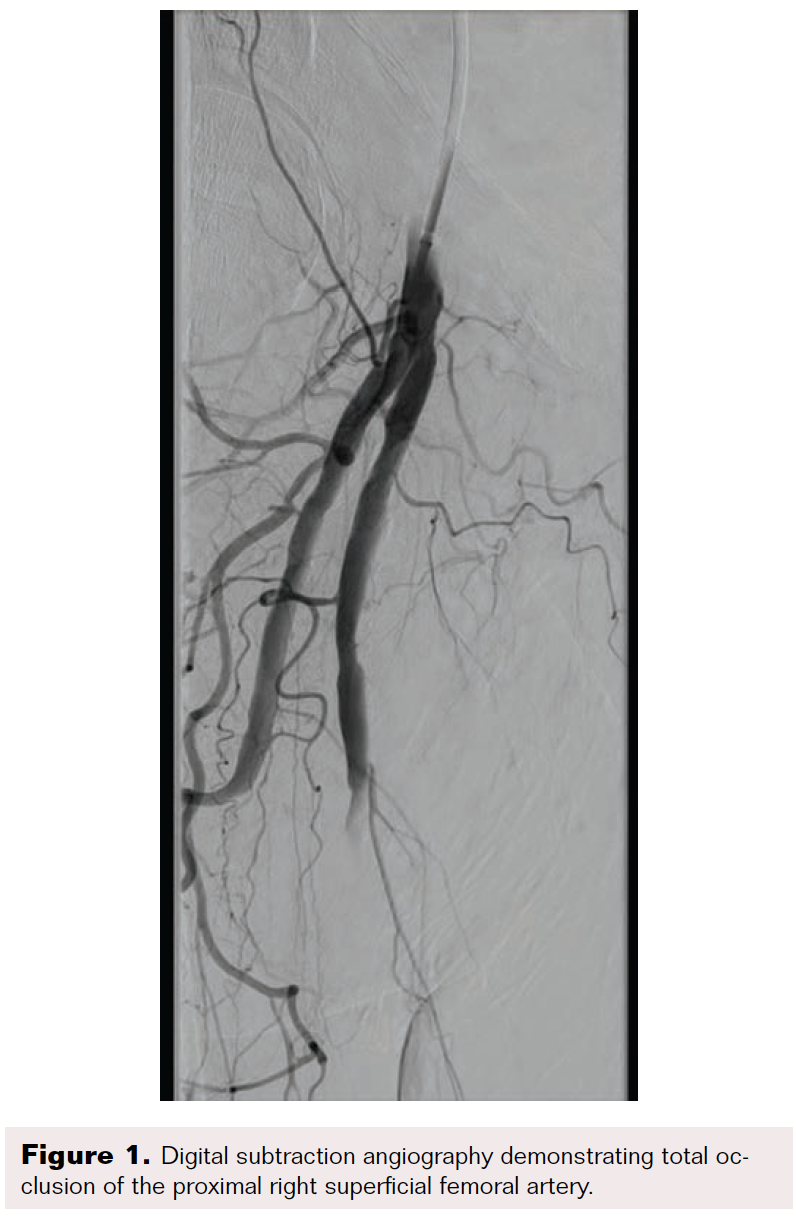

A 70-year-old man was referred for consideration of right lower extremity (RLE) intervention after initially presenting with resting ischemic pain and early tissue necrosis of the metatarsals, consistent with critical RLE ischemia. The patient was taken to the catheterization lab, where contralateral left common femoral artery (CFA) access was gained using a Micropuncture needle (Cook Medical) under ultrasound guidance. A 6F, 11 cm arterial sheath was placed into the artery over a guidewire. The right common iliac artery was engaged using a 5F internal mammary artery catheter; a 0.035" stiff-angled Glidewire (Terumo Interventional Systems) was then advanced to the right CFA. Peripheral angiography of the RLE was performed, demonstrating a total occlusion of the superficial femoral artery (SFA) as well as total occlusion of the popliteal artery and all three infrapopliteal vessels (Figure 1 and Figure 2). The 6F sheath was then exchanged over the Glidewire for a 6F, 45 cm sheath. At this time, anticoagulation was initiated with intravenous unfractionated heparin at 80 units/kg to achieve an activated clotting time (ACT) > 250 seconds.